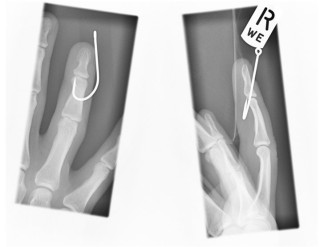

Safety

The Hawg Pockets® fishing lure guard protects against dangerous fish hook injuries by keeping the fish hooks as far away as possible from your body and those around you. One's personal fishing safety and the fishing safety of your kids, spouse and fishing buddies should always be foremost in the angler's mind.

According to Dr. Kevin Wakeman of Lutheran General Hospital in Wheaton, Illinois, each Hospital Emergency Room in a heavily fished area treats more than 600 fish hook injury cases per year! That's almost two cases each day! And these hospital visits are for major fish hook puncture injuries!

Don't let you, your fishing buddy, your family or your pet become a fish hook injury statistic!